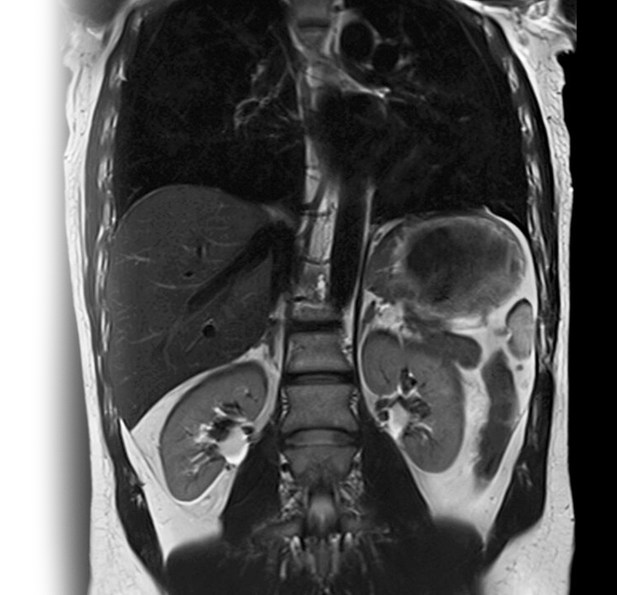

Магнитно-резонансная томография брюшной полости + МР холангиография с контрастированием – важный метод исследования с введением контрастного вещества, который позволяет визуализировать печень, почки, надпочечники, селезенку, желчный пузырь, поджелудочную железу, верхние отделы надпочечников, лимфатические узлы, желчные протоки.